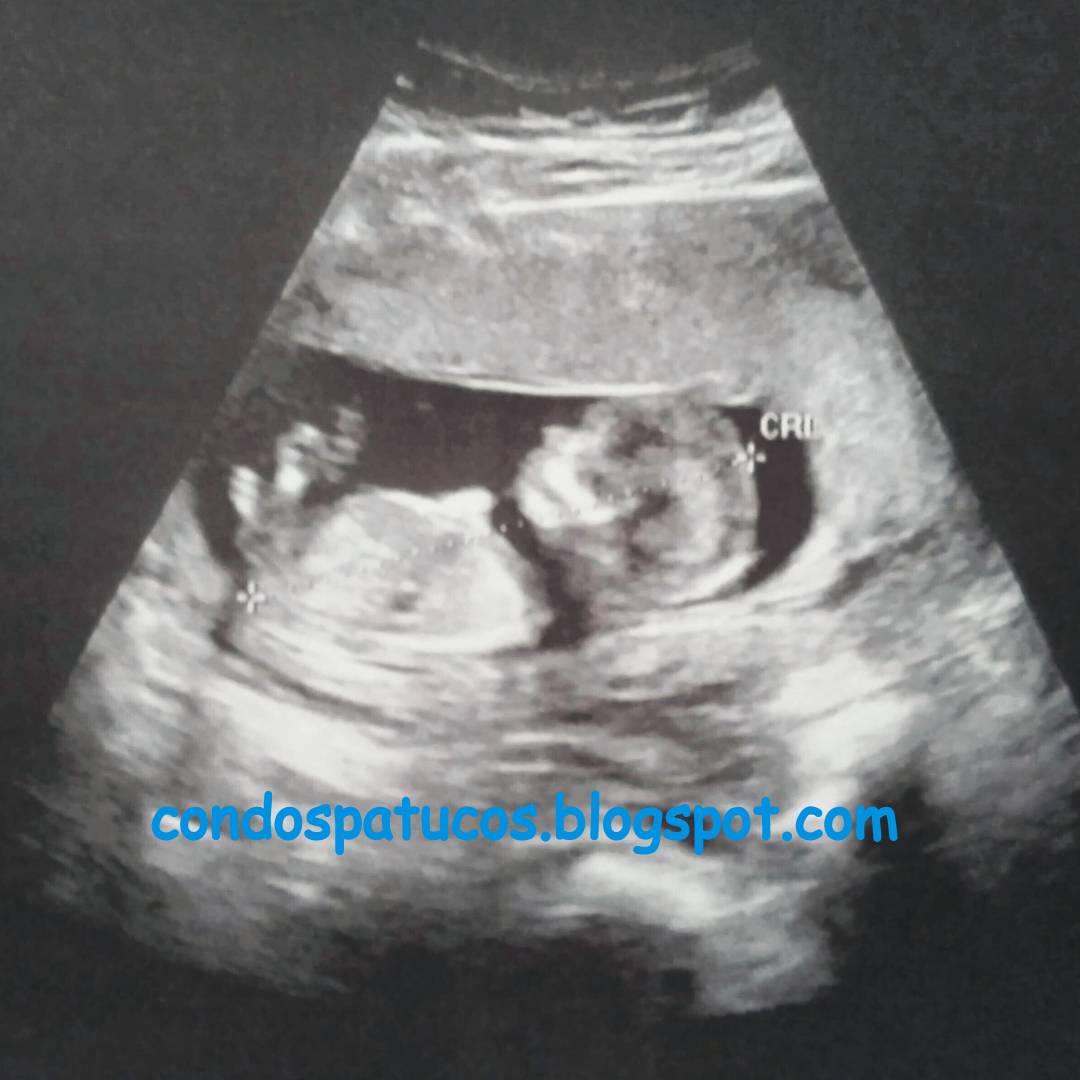

Y aquí el Cachorrín 2.0 trabajando a destajo para fabricarse unos órganos vitales.